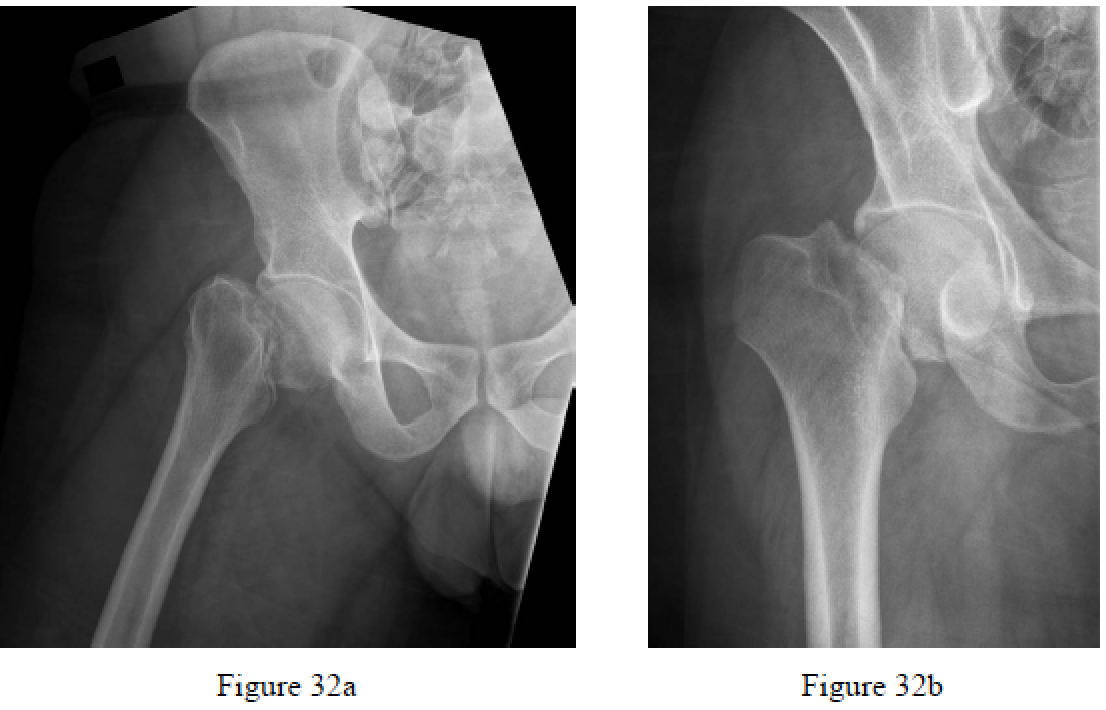

Chammout GK, Mukka SS, Carlsson T, Neander GF, Stark AW, Skoldenberg OG. Total hip replacement versus open reduction and internal fixation of displaced femoral neck fractures: a randomized long-term follow-up study. J Bone Joint Surg Am. 2010

follow-up study. J Bone Joint Surg Am. 2012 Nov 7;94(21):1921-8. PubMed PMID: 23014835.

arthroplasty for displaced fractures of the neck of the femur. Functional outcome for 450 patients at two

years. J Bone Joint Surg Br. 2002 Mar;84(2):183-8. PubMed PMID: 11922358.